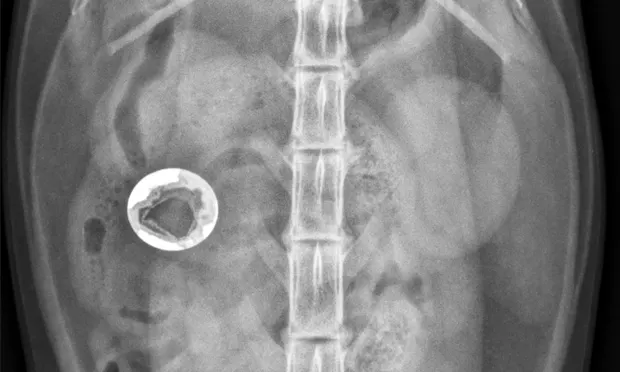

Radiographic features of small intestinal mechanical obstruction depend on its completeness, location, and duration.2 Whereas metallic FBs or those with mineral content are easily recognized within the GI lumen (Figure 1), nonmineralized, nonmetallic objects (eg, cloth) within the GI tract are more difficult to identify (Figure 2). Some may be recognized by their geometric shape. The most consistent sign of mechanical obstruction is variable dilation of intestinal loops proximal (orad) to the obstruction (described as a mixed population of small intestine; Figure 2). Determination of small intestinal diameter can be made by comparing it to the L5 vertebral body height in dogs.3 Values greater than 1.6 are suggestive of obstruction (Figure 2A). In cats, a ratio of the maximum small intestinal diameter to vertebral end plate height of L2 greater than 4 indicates a high likelihood of intestinal obstruction.4

Qualitative assessment of intestinal size by experienced clinicians may be as accurate in determining the presence of mechanical obstruction as calculation of ratios. Obstructed intestine usually contains fluid and gas; however, if the obstruction is orad, reflux into the stomach can occur and limited intestinal distension may be apparent. More distal (aborad) or more complete obstruction leads to greater dilation. Stacking of intestinal loops occurs with more severe dilation as segments become increasingly crowded in a relatively smaller space (Figure 2B).

FIGURE 2

Right lateral (A) and VD (B) abdominal radiographs of a Labrador retriever with an obstructive ileus. A FB (sock) is present within a dilated small intestinal loop in the right caudoventral abdomen (arrows). The dashed lines outline a fluid-filled loop measuring 2.7 cm and a gas-filled loop measuring 2.4 cm, compared to the height of L5 (Asolid line, 1.1 cm);  the resulting ratios of 2.4 and 2.2, respectively, are much greater than the upper limit of 1.6 for normal small intestine to L5 height ratio. Several stacked gas-filled loops of small intestine are present in the left midabdomen (B).